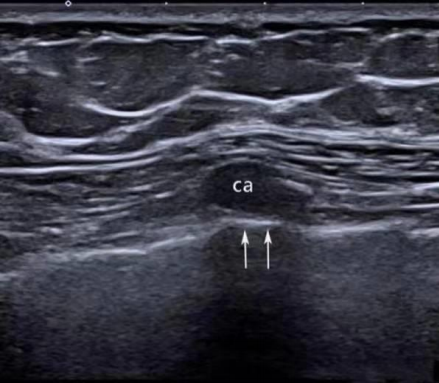

胸部肋软骨导致深方的胸膜线向前隆起(箭头):

由上述声像图得知:脂肪内声速低于1540m/s,声像图上其后方的组织会向深方移位,软骨内声速远高于1540m/s,声像图上其后方的组织会向前方移位。